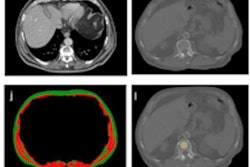

The study included 100 patients with confirmed COVID-19 who had ongoing symptoms more than 30 days after diagnosis and 106 healthy controls. Patients were categorized as ambulatory (67%), hospitalized (17%), or requiring intensive care (16%); the team gathered information on symptoms, pulmonary function tests, and chest CT imaging for each individual. Patients were imaged on chest CT using an expiratory protocol, a postexhalation scan that helps assess air trapping.

The most common chest CT findings in patients experiencing postacute sequelae of COVID-19 were air trapping (58%) and ground-glass opacities (51%); ground-glass opacities were more common among patients who required hospitalization in the intensive care unit (ICU) (94%) compared with ambulatory patients (36%).

The mean percentage of total lung area affected by air trapping post-COVID-19 was comparable across disease severity categories, with 25.4% of ambulatory patients, 34.6% of hospitalized patients, and 27.3% of intensive care patients experiencing the condition. In contrast, mean percentage of total lung affected by air trapping post-COVID-19 was only 7.5% in the healthy control group.